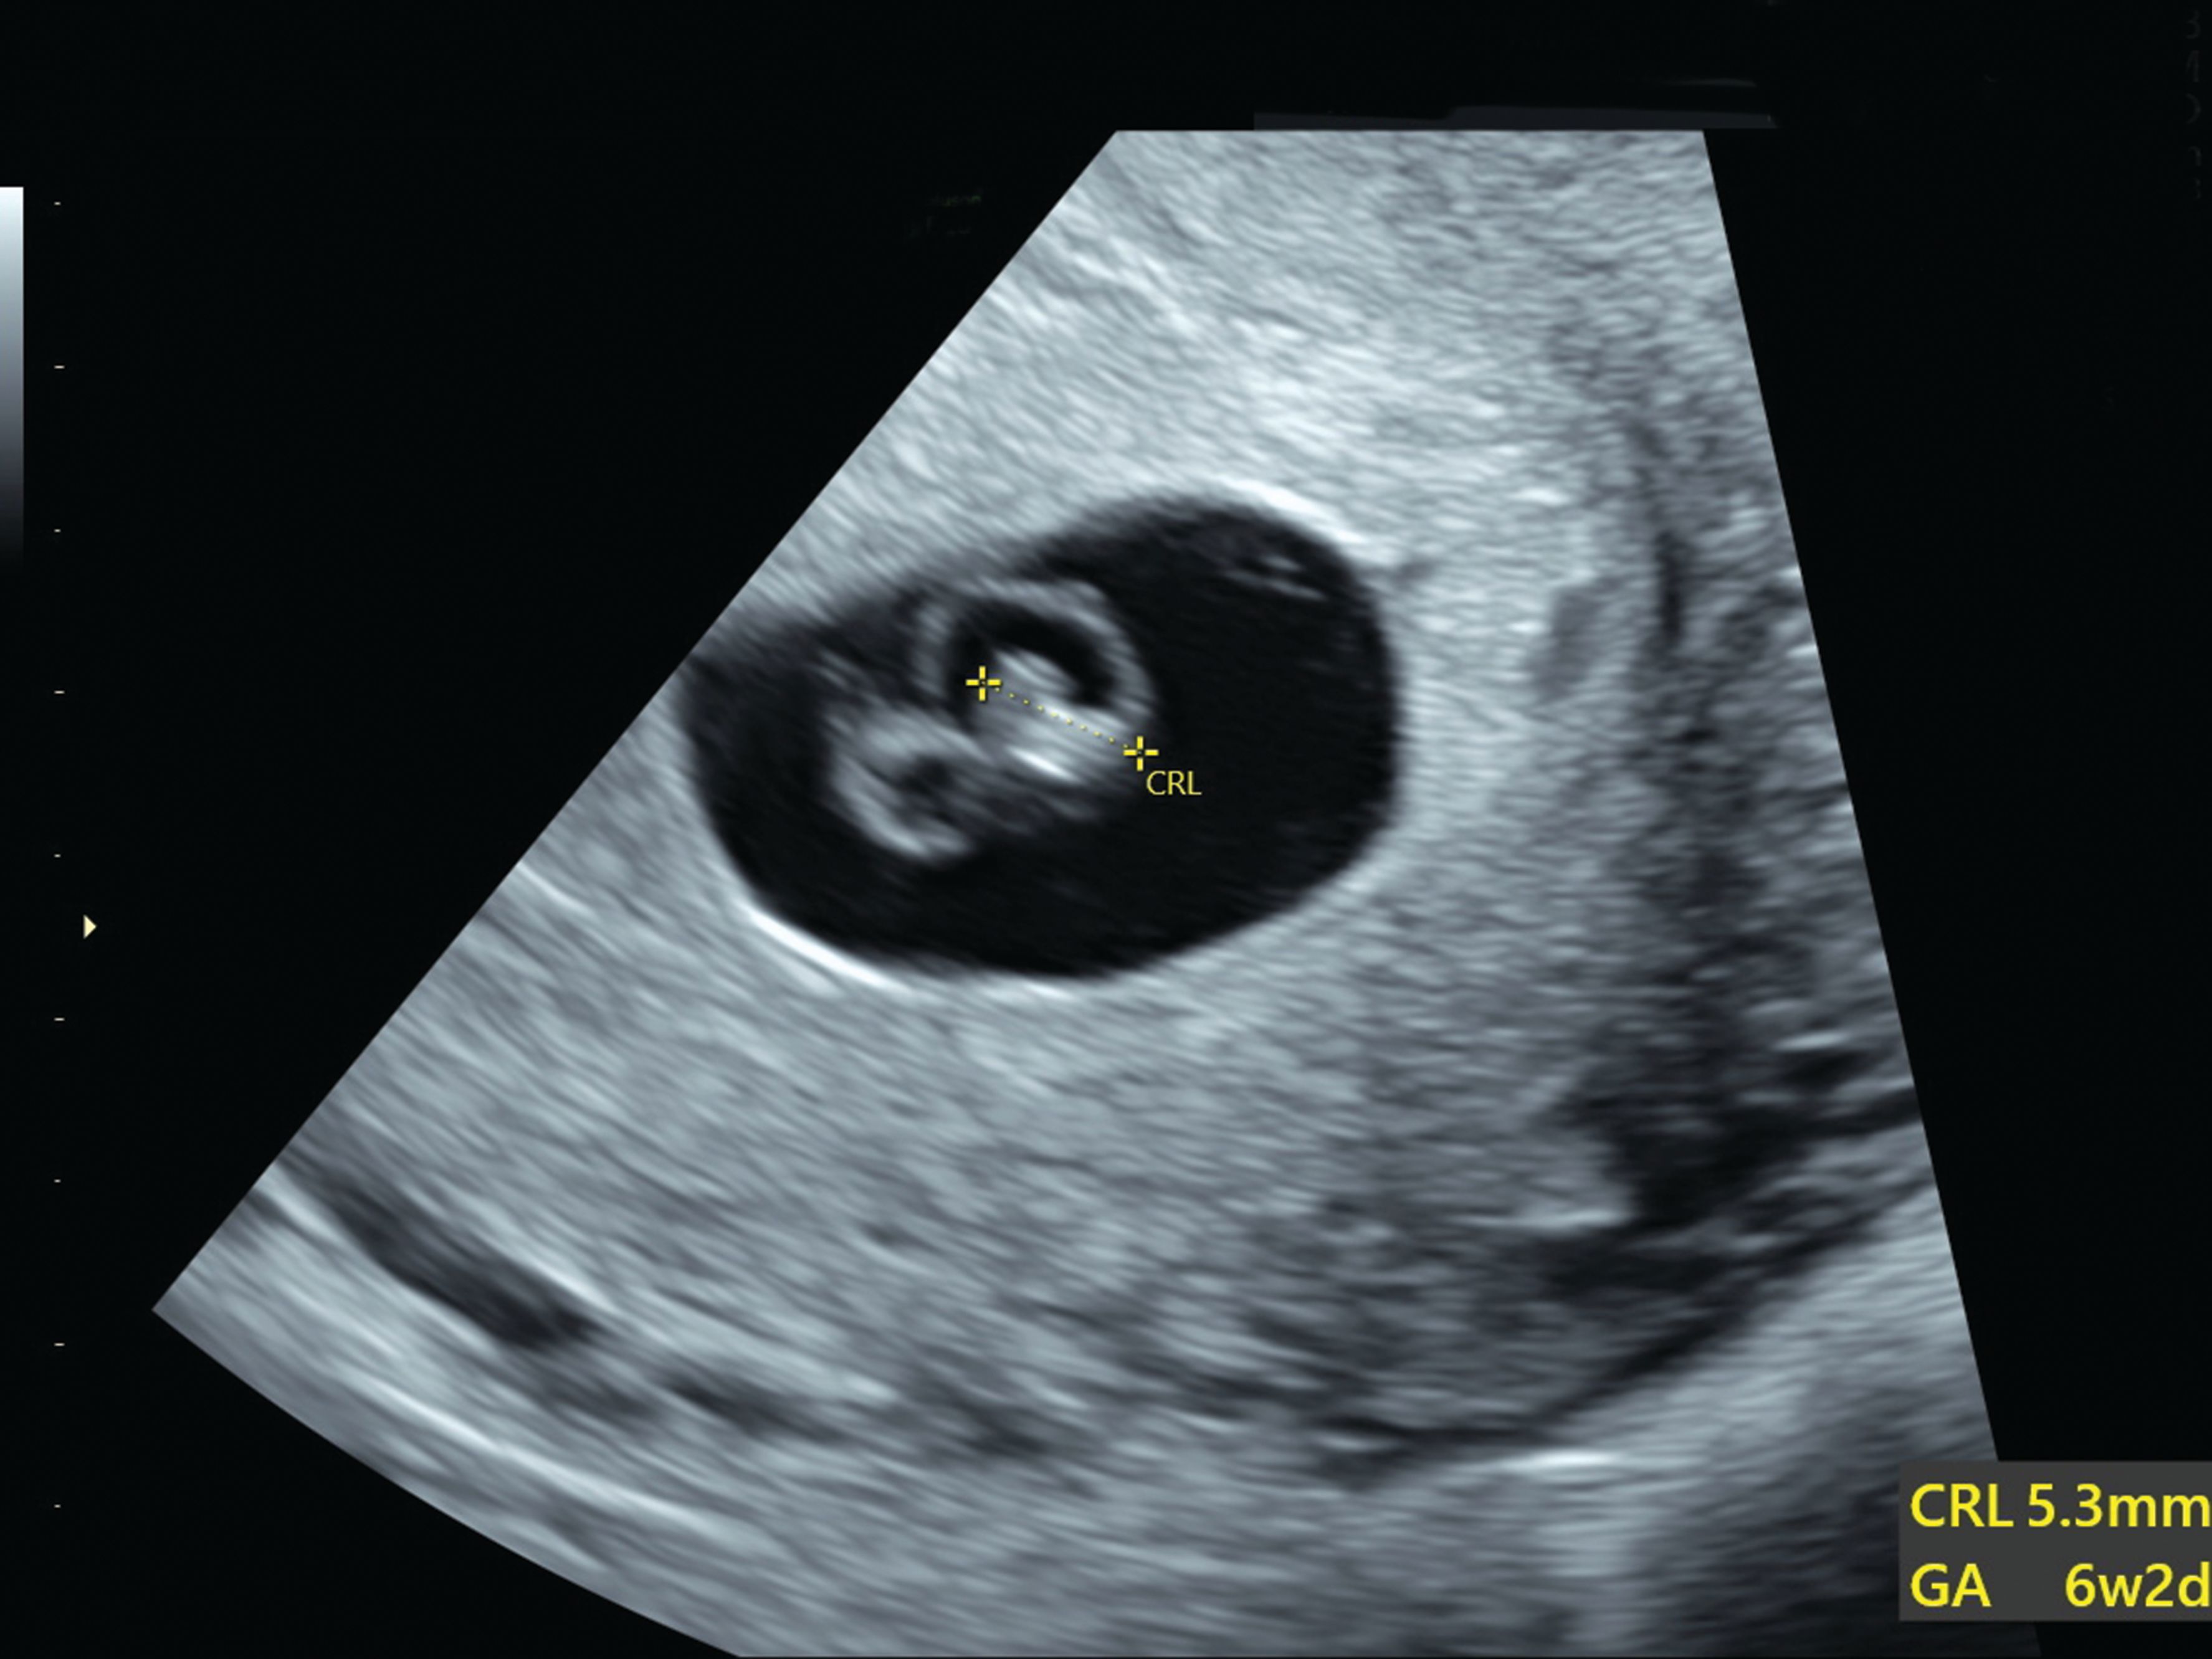

Miscarriage At 6 Weeks: Words Of Hope & Understanding

Miscarriage is very common in the first few weeks of pregnancy. A complete miscarriage is likely. Learn more about miscarriage, or the early and spontaneous...